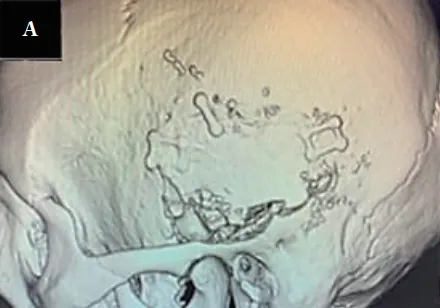

患者是一名51岁男性,一年前被确诊为听神经瘤。尽管未出现面神经麻痹,但左耳听力已严重受损至105dB,生活陷入“半静默”状态。MRI检查显示,肿瘤直径达24mm,并已经侵入内耳道。

入院时T1-加权项磁共振成像显示,延伸到内听道的桥脑角均匀增强。